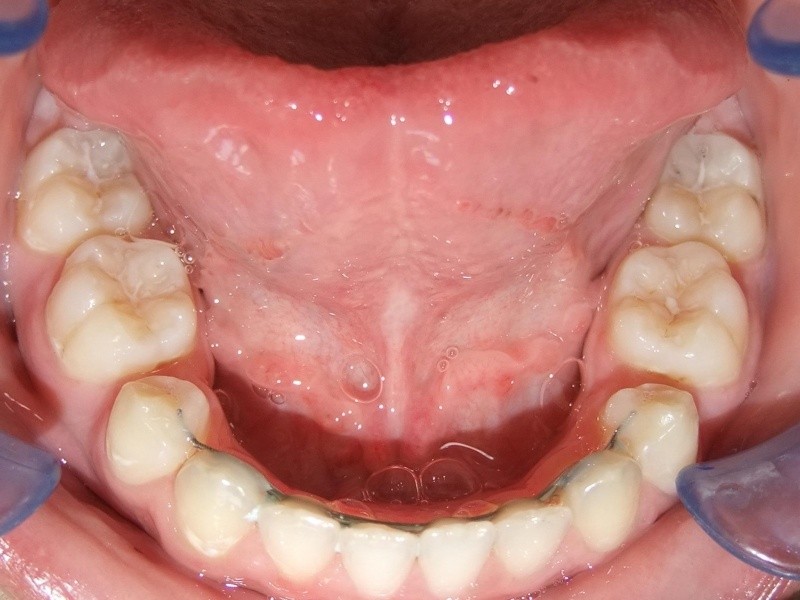

eindfoto

Retentie fase: Wrap en C-CBar